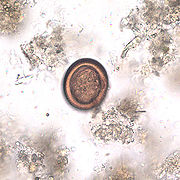

Los huevos (30 - 40 µm), son la forma infectiva para los hospederos intermediarios (principalmente ungulados como ovejas, cerdos, ganado vacuno, cabras, caballos) y otros que pueden tener un papel en el ciclo biológico (marsupiales, roedores, carnívoros). Los humanos constituyen es hospederos accidentales.

En la hidatidosis quística, 5 días después de la ingestión de huevos, el metacestodo vesicular presenta dos capas, una interna, la germinativa, una externa, acelular (endoquiste), el cual mide 60 - 70 µm. La inducción de una reacción granulomatosa en el hospedero da lugar a la formación de una tercera capa, de tejido conectivo (periquiste - capa adventicia). El contenido líquido es claro, casi como "agua de roca". La capa germinal da lugar a vesículas en las que se desarrollan protoescólices, con 4 ventosas y corona de ganchos (escólices). Estas vesículas pueden encontrarse adheridas a la pared o libres, en el líquido. El conjunto de restos membranales, protoescólices, constituyen la denominada "arenilla". El tamaño del quiste oscila entre 1 - 15 cm, pero puede ser mayor, con varios litros de líquido en su interior. Su desarrollo es lento, y con el tiempo puede dar lugar a una masa ocupativa de importancia. El contenido líquido es habitualmente claro. El líquido quístico es una mezcla compleja de glucolipoproteínas, carbohidratos, aminoácidos y sales y productos del metabolismo del metacestodo en una base del 98% de agua, con pH neutro. Algunos de sus componentes provienen del hospedero, principalmente albúmina e inmunoglobulinas.

Se ha utilizado la punción de aguja fina con guía ultrasonográfica en casos dudosos de equinococosis quística para la búsqueda y visualización directa por microscopia de protoescólices, ganchos, y análisis de posibles antígenos o DNA. Se recomienda iniciar el tratamiento con albendazol en días previos al procedimiento y continuarlo al menos durante un mes cuando el diagnóstico es hidatidosis. También es posible el estudio histopatológico de la pieza extraída por cirugía. Los protescólices también pueden ser demostrados en esputo o mediante lavado broncoealveolar.